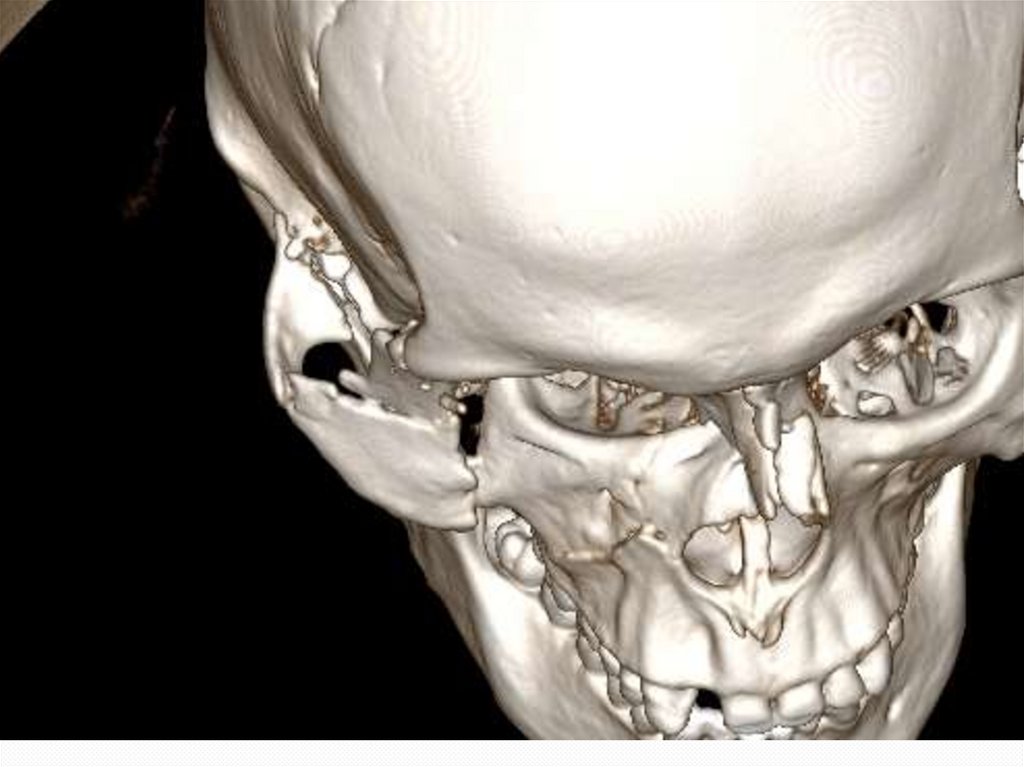

12. Клинический случай № 2! Поскользнулся, упал, потерял сознание, очнулся …

Пациент С. 40 лет.